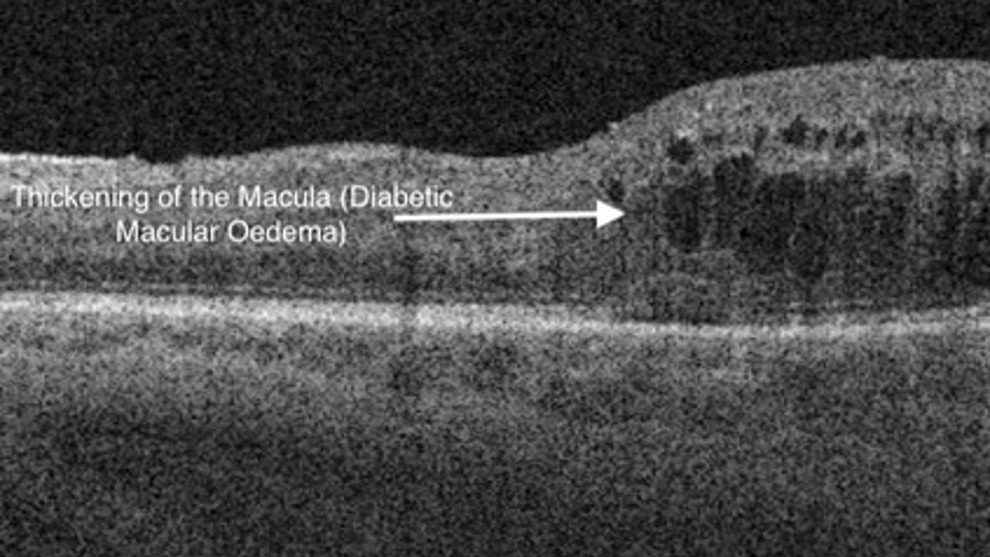

Diabetic macular oedema is the most common complication, where blood vessels in the macular area leak fluid and cause blurred or distorted central vision.